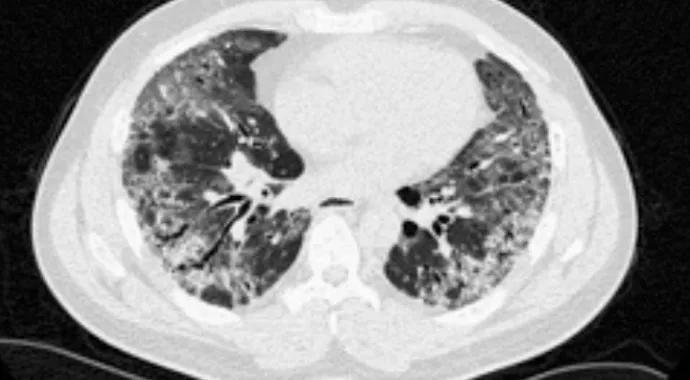

In our cohort of 42 patients with anti-PM-Scl antibody, ILD was described on thoracic high-resolution CT scan (HRCT) in 27 patients (64.3 percent). HRCT images available for review in 23 patients revealed predominantly fibrotic NSIP (observed in 56.5 percent) (Figure 2), but cellular NSIP (Figure 3), organizing pneumonia and usual interstitial pneumonia were also seen. Fifteen patients had follow-up HRCT images available (mean follow-up, 46.5 months); among these patients, 40 percent of those with initial cellular NSIP progressed to fibrotic NSIP, as did all patients with organizing pneumonia.

Figure 2. Mixed ground-glass opacification and reticular pattern in a patient with fibrotic nonspecific interstitial pneumonia.